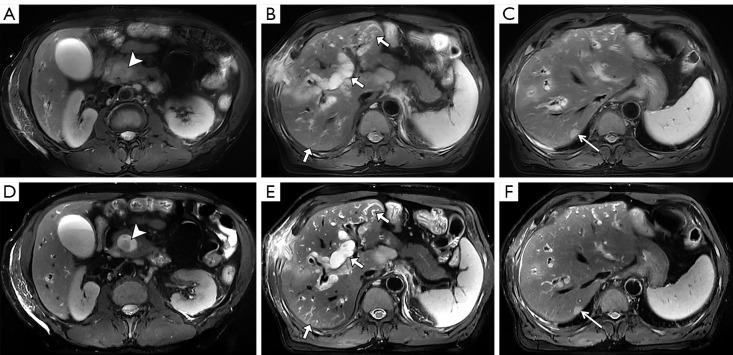

Magnetic resonance imaging (MRI) plays a crucial role in the diagnosis of abdominal conditions. A comprehensive assessment, especially of the liver, requires multi-planar T2-weighted sequences. To mitigate the effect of respiratory motion on image quality, the combination of acquisition and reconstruction with motion suppression (ARMS) and respiratory triggering (RT) is commonly employed. While this method maintains image quality, it does so at the expense of longer acquisition times. We evaluated the effectiveness of free-breathing, artificial intelligence-assisted compressed-sensing respiratory-triggered T2-weighted imaging (ACS-RT T2WI) compared to conventional acquisition and reconstruction with motion-suppression respiratory-triggered T2-weighted imaging (ARMS-RT T2WI) in abdominal MRI, assessing both qualitative and quantitative measures of image quality and lesion detection.

There ACS-RT T2WI protocol had a significantly reduced median scanning time compared to the ARMS-RT T2WI protocol (148.22±38.37 13.86±1.72 seconds). However, ARMS-RT T2WI had a higher PSNR than ACS-RT T2WI (39.87±2.72 38.69±3.00, P<0.05). Of the 201 liver lesions, ARMS-RT T2WI detected 193 (96.0%) and ACS-RT T2WI detected 192 (95.5%) (P=0.787). Of the 97 biliary system lesions, ARMS-RT T2WI detected 92 (94.8%) and ACS-RT T2WI detected 94 (96.9%) (P=0.721). Of the 110 pancreatic lesions, ARMS-RT T2WI detected 102 (92.7%) and ACS-RT T2WI detected 104 (94.5%) (P=0.784). The CR analysis showed the superior performance of ACS-RT T2WI in certain lesion types (hemangioma, 0.58±0.11 0.55±0.12; biliary tumor, 0.47±0.09 0.38±0.09; pancreatic cystic lesions, 0.59±0.12 0.48±0.14; pancreatic cancer, 0.48±0.18 0.43±0.17), but no significant difference was found in others like focal nodular hyperplasia (FNH), hepatapostema, hepatocellular carcinoma (HCC), cholangiocarcinoma, metastatic tumors, and biliary calculus.

ACS-RT T2WI ensures clinical reliability with a substantial scan time reduction (>80%). Despite minor losses in detail and SNR reduction, ACS-RT T2WI does not impair lesion detection, marking its efficacy in abdominal imaging.